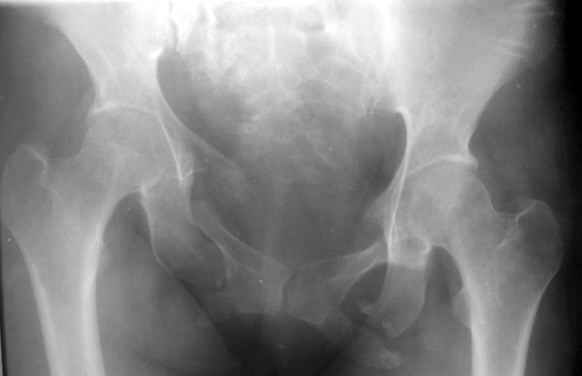

Застарелая деформация таза |

Вопрос Уральскому Пельвиоцентру: через год после травмы, довольно симпатичная женщина, болей нет, только ходит призрамывая на правую ногу и сидит криво, мышечная ассиметрия практически не выражена, хотя слабость справа есть. Легко компенсируется подкладкой стельки 1,5 см с выраженным клиническим эффектом. Посылаю снимки с вопросом - можно ли устранить деформацию в Вашем аппарате, если можно - то поподробнее. Снимки с разницей во времени почти 1 год. Жду ответа как соловей лета. ЛАФ.

Дело в том, что там непревильно сросшийся перелом боковых масс крестца - Делать ли остетомию - продолженную репозиуию в аппарате, внутреннюю фиксацию переднего и заднего полукольца или вместо всего этого одномоментно удлинить бедро на 1,5 см, в крайнем случае добавить резекцию седалищного бугра слева - прямее будет сидеть.? ЛАФ.

Привет! Случай типичный при такой травме, когда накладывают переднюю раму аппарата, но репозиции не достигают и игнорируют повреждение задних отделов. Интересно узнать всю историю поподробнее, где и как лечилась, сроки, была ли информация у больной, что ей можно было помочь гораздо раньше и с большим эффектом.

На счет жалоб: к году полутора при этом повреждении больные приспосабливаются к новым условиям и активно предъявляют жалобы, как правило, только на боли, с которыми они смирились и хромоту. Перелом боковой массы крестца или срастается или образует достаточно спаек для стабилизации повреждения в отличие от чистых разрывов КП сочленения.

Однако при расспросе картина становится более ясной, т.к. выявляются ограничения в ходьбе, сидении, лежании и способности к труду. Мы пользуемся универсальными шкалами, хорошо бы узнать ее баллы по Majeed. Для уточнения диагноза и степени сращения необходимы дополнительные проекции inlet, outlet и обязательно КТ таза с шагом 0,5мм. Не плохо было бы и общий вид узреть - фас, сзади и стоя на одной ноге.

Объем хирургического пособия зависит от этих данных.

Привожу пример лечения больного с 7 месячной деформацией. Отеотомии - аппарат - внутренняя фиксация.

Рентгенограммы до и через месяц после окончательной стабилизации. Потом поищу более поздние снимки.